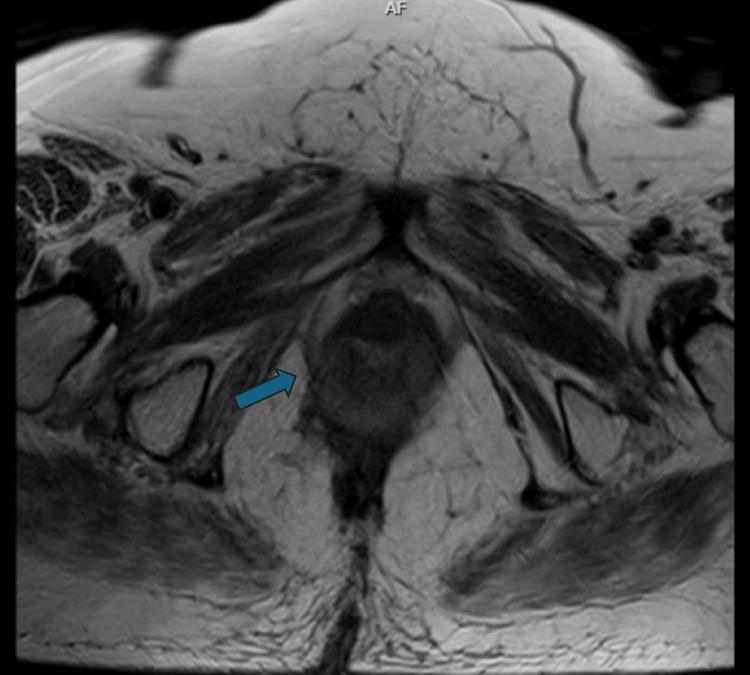

Anorectal melanoma (ARM) is a rare entity with aggressive biological behavior and poor prognosis. Clinically, ARM presents with atypical symptoms, such as anal pain and bleeding, thus often being misdiagnosed as a benign anorectal pathology and leading to delayed diagnosis. We present a case of a 73-year-old female patient with stage I ARM, treated successfully with a combination of neoadjuvant-adjuvant immunotherapy (nivolumab, an anti-PD-1 monoclonal antibody) and abdominoperineal resection. The patient is disease-free at a five-year follow-up after the operation, suggesting that long-term targeted immunotherapy offers a durable and promising response. This case highlights the critical role of a multidisciplinary approach, involving specialists in ARM surgery and systemic therapies, to improve prognosis and ensure an optimal quality of life for patients with ARM. Given the limited scientific evidence, further prospective and randomized trials are required to develop effective systemic therapies and improve the survival of patients with ARM.

摘要

肛管黑色素瘤(ARM)是一种罕见的疾病,具有侵袭性生物学行为且预后较差。临床上,ARM表现为非典型症状,如肛门疼痛和出血,因此常被误诊为良性肛管病变,导致诊断延迟。我们报告一例73岁I期ARM女性患者,通过新辅助-辅助免疫治疗(纳武单抗,一种抗PD-1单克隆抗体)联合腹会阴切除术成功治疗。术后五年随访时患者无疾病,表明长期靶向免疫治疗可提供持久且有前景的反应。该病例突出了多学科方法的关键作用,包括ARM手术和全身治疗专家,以改善预后并确保ARM患者的最佳生活质量。鉴于科学证据有限,需要进一步进行前瞻性和随机试验,以开发有效的全身治疗方法并提高ARM患者的生存率。